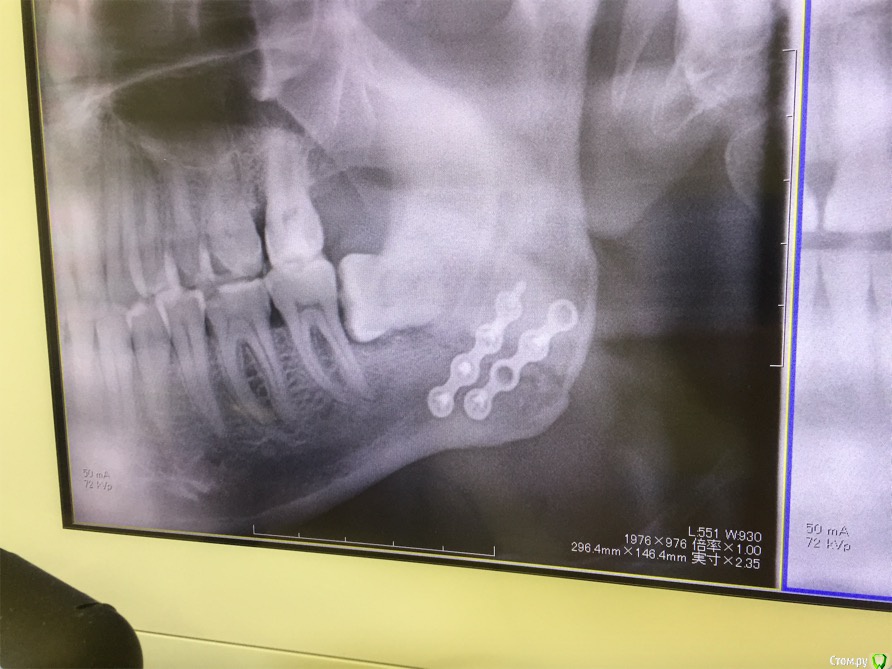

cinovka Опубликовано 10 сентября, 2015 Поделиться Опубликовано 10 сентября, 2015 Здравствуйте. Помогите советом. 15 августа получил перелом нижней челюсти с левой стороны в районе 7-8го зуба.25 числа наложили титановую пластину на место перелома и зашинировали. 3 сентября сняли шины. Разрез делали в ротовой полости и снаружи, для закрутки шурупов.Наружную рану опять вскрыли 1го сентября, т к началось нагноение. Гной выходит постоянно уже 9й день. все болит. зуб мудрости лежит в десне и очень сильно болит.Прошла неделя после снятия шин, а рот также не открылся. максимально открывается на 1-1,2 см.Я нахожусь за границей и врач мой толком ничего не обьясняет.Ответьте пожалуйста на следующие вопросы : 1) Кода пройдет нагноение? И почему оно произошло? (антибиотики, повязки и полоскания постоянные). 2) Когда откроется челюсть? 3) Когда можно будет удалить лежачий зуб мудрости? Снимки номер 1,2,3,4 сделаны до операции 17 августа.Снимки номер 5,6 сделаны сегодня 10 сентября. Заранее спасибо за ответы. Жду с нетерпением. Алексей. Ссылка на комментарий

kriokov Опубликовано 10 сентября, 2015 Поделиться Опубликовано 10 сентября, 2015 1. Зуб надо удалять в ближайшее время, возможно он и пддерживает гноетечение2. Нужен врач челюстно лицевой хирург, чтоб оценить не только снимки но и клинику очно3. Фрагменты челюстей по снимкам в правильном положенииИщите врача 5 Ссылка на комментарий

колесников Опубликовано 10 сентября, 2015 Поделиться Опубликовано 10 сентября, 2015 (изменено) Ошибка в тактике. Зубы находящиеся в линии перелома удаляются.8ки надо срочно удалять. Вопрос с костным фрагментом слева,возможно он секвестрируется. Рот откроется не скоро. И вообще обычно делается межчелюстное шинирование в таком случае на месяц. Антибиотик надо поменять. Обратитесь в стационар. Отделение челюстно лицевой хирургии. Свяжитесь со страховой компанией, если вы заграницей. Изменено 10 сентября, 2015 пользователем колесников 1 1 Ссылка на комментарий

kriokov Опубликовано 10 сентября, 2015 Поделиться Опубликовано 10 сентября, 2015 Вопрос с костным фрагментом слева,возможно он секвестрируется. чего пациента пугать. Там только два фрагмента, большой и малый, две "линии перелома"- это просто обычная картинка , редко когда ломают челюсть как по линейке, равнозначно с вестибулярной и язычной поверхности. Короче-- не секвестр 3 Ссылка на комментарий

ПалСаныч Опубликовано 10 сентября, 2015 Поделиться Опубликовано 10 сентября, 2015 С колесниковым не согласен категорически. Полностью поддерживаю криокова. Это не секвестр, это наложение двух линий перелома с внутренней и наружной стороны. Если б ко мне попал пациент с такой проблемой, то я предложил бы ему такую тактику: 1 пластины снять нафиг, потому чо они там не работают, ибо наложены стнарушением правил остеосинтеза, а так же потому что в ране гной; 2 во время снятия пластин через разрез задренировать рану и провести антибактериальную терапию; 3 наложить опять шины если есть подвижность отломков после снятия пластин. 4 зуб убрать вместе с пластинами. Все написанное ИМХО. 6 1 Ссылка на комментарий

cinovka Опубликовано 11 сентября, 2015 Автор Поделиться Опубликовано 11 сентября, 2015 У Вас остеомиелит челюсти.Если зуб не удалить,перелом не зарастёт никогда.Надо решать этот вопрос незамедлительно.Вы в каком городе находитесь сейчас?Есть ли возможность вернуться в Москву?Вы уверены: что у меня остеомиелит? Врач сказал, что его нет. Предоставление снимки сделаны круговым рентгеном, а не просто с левой стороны. Врач пояснил, что поэтому кажется что там две трещины. Возможно Вы в курсе, извините. Ссылка на комментарий

kriokov Опубликовано 11 сентября, 2015 Поделиться Опубликовано 11 сентября, 2015 1. По Вашим жалобам и клинике тянет на остеомиелит, точно только очно можно2. Вам сделали оптг, аппарат ходил кругом как Вы выразились. При таком снимке, да и при выполнении снимков другими методами линий перелома кажется что две, на самом деле плоскость перелома одна (ПалСаныч выше описал)3.учитывая, что гноетечение и со стороны полости рта в обл 8 и снаружи из послеоперационной раны и отек лица держится выраженный я бы члх еще раз потревожил, не решите на месте, надо возвращаться. Имхо Ссылка на комментарий